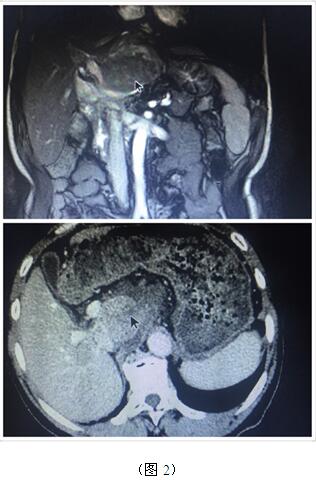

70歲高齡的曹奶奶是一個膽內(nèi)膽管結石、膽總管結石、膽囊結石的高齡患者,由于結石部位多發(fā)(圖1),當?shù)蒯t(yī)院多次住院治療,均建議開大刀切除部分肝臟;同樣患肝臟腫瘤的張爺爺,由于腫瘤位于肝臟尾葉,而且壓迫腹腔大血管(圖2),尋遍多家醫(yī)院都只能開腹手術切除,聽說衡陽市中心醫(yī)院腹腔鏡手術技術成熟遂慕名而來。肝膽外科周玖橋主任和李鑫副主任醫(yī)師仔細分析病情后決定為倆位患者行3D腹腔鏡手術。